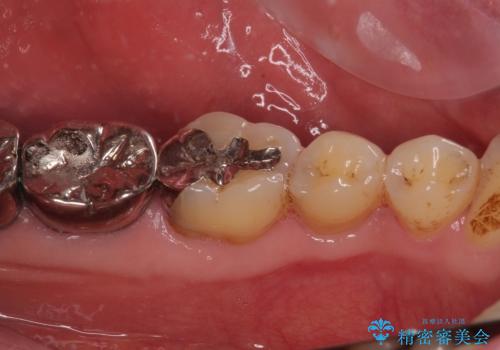

- 奥歯で食事がとれないくらいに痛むとのことで来院された患者です。

診察の結果、既に根管治療をされている第二大臼歯の根尖部に大きな病変があり、それが痛みの原因であるため、根管治療が必要と判断されました。

速やかに根管治療を行い、痛みの消退を確認の後、オールセラミッククラウンにて補綴治療を行うこととしました。